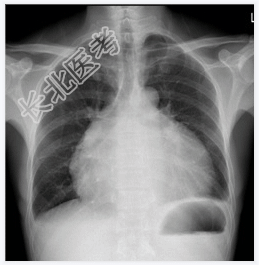

- [材料题] 患者,男性,51岁,腹胀1月余入院。查体:腹围增大,移动性浊音阳性。心界扩大,心音遥远。行胸部平片检查。

- 简答题1、诊断是什么?

- 简答题2、心包积液的常见原因有哪些?

- 简答题3、心包积液的典型临床表现是什么?